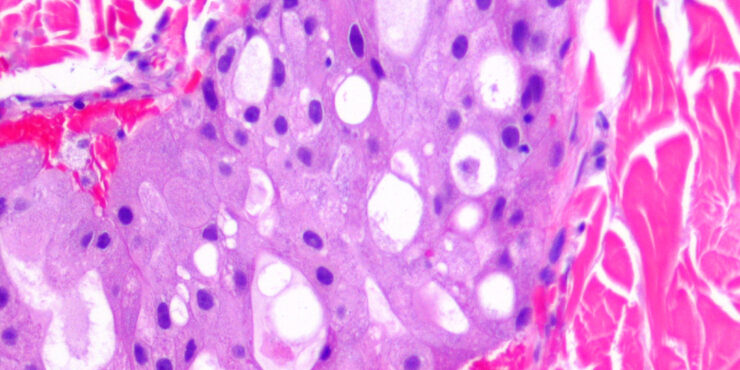

merkel-cell-carcinoma